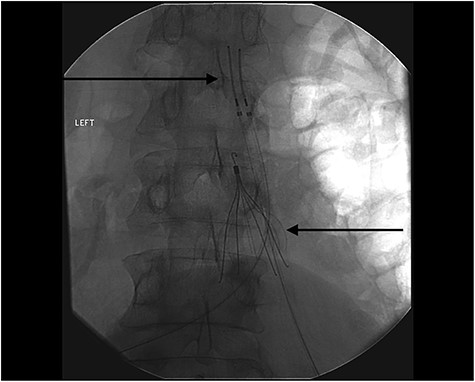

After the case was discussed with multiple teams and deemed too unsafe for surgery, the patient was admitted to the intensive care unit, bilateral thrombolytic catheters were placed from the legs to above the IVC, and he was treated with intravascular thrombolytic (Alteplase and Heparin) therapy (Fig. 3). On Day 5, he developed bloody emesis and was noted to have a hemoglobin drop from 12 to 8 g despite blood transfusions. The patient was resuscitated, and an EGD demonstrated a blackened esophagus of the entire esophagus with no involvement into the stomach (Fig. 4). Considering these findings, transthoracic echocardiogram (TTE) and chest computed tomography (CT) angiogram (CTA) were performed, which revealed patent foramen ovale (PFO) with small right to left shunt and an edematous esophagus and duodenum with no perforation or arterial inflow problem, respectively. No intervention was performed. The patient eventually stabilized and a repeat EGD a week later showed resolution of the ischemic esophagus. Patient was started back on liquid diet, which was advanced to solid diet and was discharged a week later.

IVC filter and bilateral intravascular catheters to administer thrombolytic (Alteplase and Heparin) therapy. The upper left corner shows the Thrombolytic Catheter and the right lower arrow shows that IVC filter.